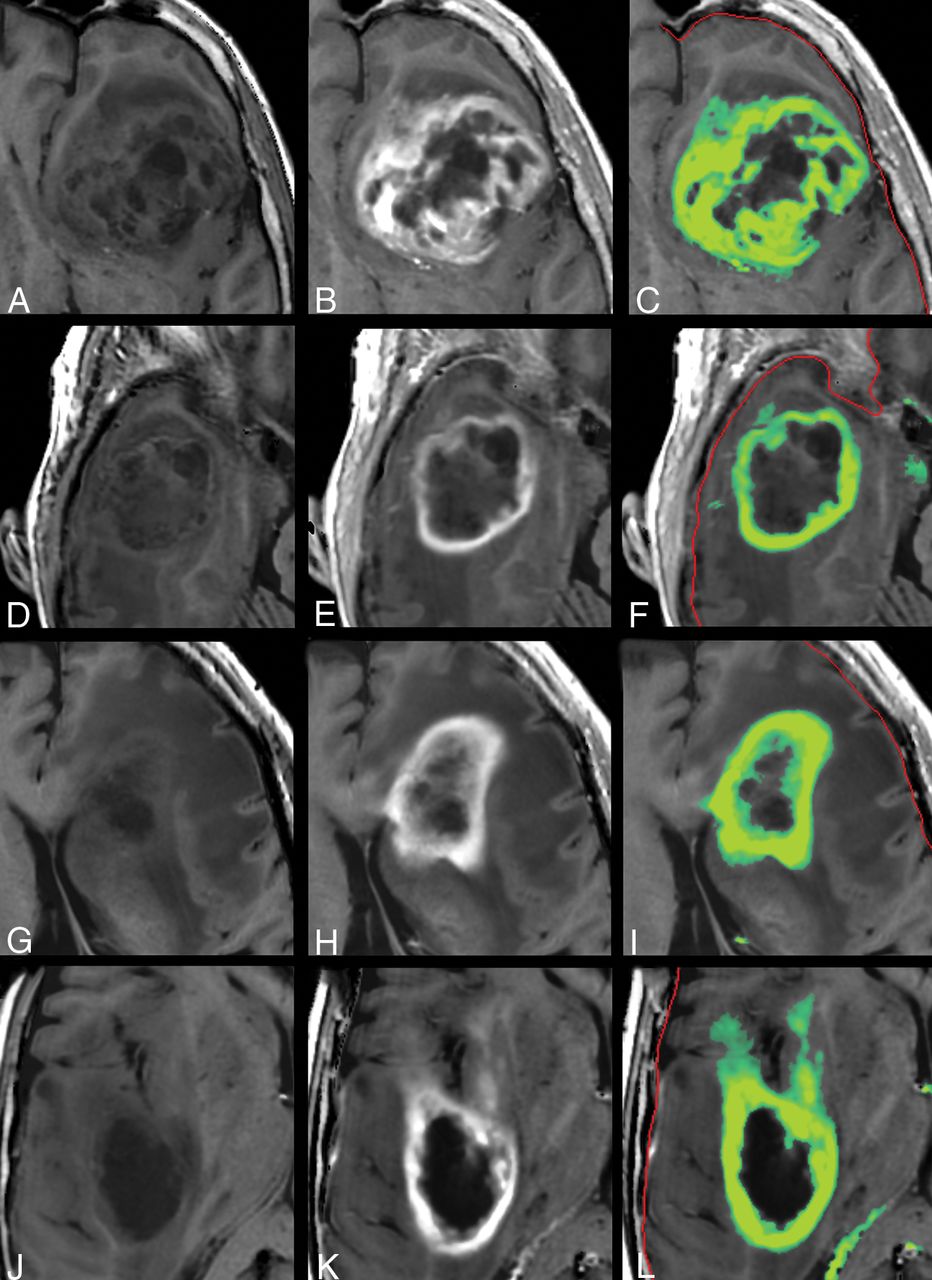

Other examples of the synthetic R1 enhancement map and low-intensity enhancement at the edges of high-intensity enhancement in gliomas. Left: native synthetic T1-weighted image. Center: post-GBCA synthetic T1-weighted image. Right: synthetic R1 enhancement map as a green overlay. The color indicates a range of dR1 of 0.2–1.0 seconds−1. The red line indicates the edge of the intracranial volume.

In 10 of 14 patients, >1 mL of tissue was found in the synthetic R1 enhancement images with an enhancement of >0.2 seconds−1 outside the drawn ROI. The mean additional tumor volume for all patients was 1.71 ± 1.28 mL, with a maximum of 4.3 mL. In comparison, the mean tumor volume within the ROIs was 63.5 ± 44.4 mL (range, 9–134 mL). More examples of the synthetic R1-enhancement maps are provided in Fig 5.

In Fig 4, the tumor in Fig 2 is zoomed-in. The native and post-GBCA T1-weighted images are shown as well as the ROI drawn by the radiologist. In Fig 4D, the synthetic R1 enhancement map is shown as a green overlay where full color corresponds to a dR1 of 1 second−1. At various places, low-intensity enhancement in the range 0.2–0.5 seconds−1 is observable outside the high-intensity enhancing tumor and drawn ROI. On average for all patients, 35.8% of the pixels touched by the drawn ROI lines had values above 0.2 seconds−1 for the synthetic R1 enhancement map and even 50.3% for the subtraction R1 enhancement map. When the ROI line was expanded with an additional margin of 1 or 2 mm, this percentage reduced to 8.0/17.4% and 2.3/8.6%, respectively (Table 2).

Zoomed part around the tumor displayed in Fig 2. Synthetic T1-weighted imaging using native data (A), synthetic T1-weighted imaging using post-GBCA data (B), the ROI line as drawn by a neuroradiologist to encapsulate the border of the enhancing tumor (C). D, Synthetic R1 enhancement map shown as a green overlay on the synthetic T1-weighted image in which full color corresponds to dR1 = 1.0 seconds−1. The minimum enhancement was set at dR1 = 0.2 seconds−1. Some low-intensity enhancement is visible outside the yellow ROI. The red line indicates the edge of the intracranial volume.